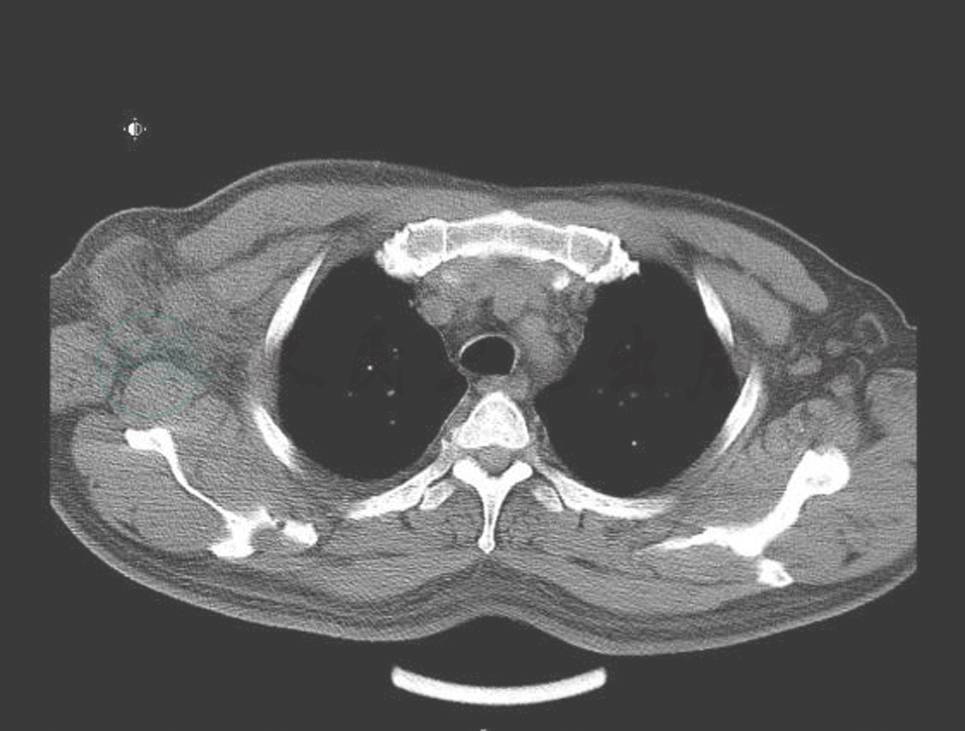

血象、血沉、结核三项、G试验、呼吸道病原及风湿免疫检查均未见异常。T-SPOT阳性。IgG 1410mg/dl,IgG4 355mg/dl。胸腔积液:送检胸水涂片及细胞病理学未见阳性结果;常规生化结果考虑为渗出液。胸部CT:右侧胸壁软组织占位并肋骨破坏及纵隔、腋窝淋巴结多发转移,不除外胸壁来源的恶性肿瘤;双肺炎症(图2、图3、图4)。小器官超声:双侧腋下多发肿大淋巴结。我院病理会诊(外院腋窝淋巴结标本):其内见血管内皮细胞增生显著。我院右侧腋窝淋巴结活检病理:Castleman病(巨大淋巴结增生症),透明血管型。免疫组化染色结果:CD3(T 细胞 +),CD20(B 细胞 +),CD21(+),CD34(血管 +),CD38(+),Ki-67(+25%~50%)。我院病理会诊(外院胸壁皮肤标本):考虑血管源性肿瘤,以上皮样血管内皮细胞瘤可能性大。我院右胸腹部皮肤活检:不除外血管肉瘤。北京协和医院病理会诊:(外院淋巴结):淋巴结结构存在,淋巴滤泡生发中心缩小,滤泡间见较多浆细胞浸润伴小血管增生。(外院皮肤):真皮胶原纤维及小血管显著增生,伴少许淋巴细胞浆细胞浸润;结合免疫组化考虑为IgG4相关性疾病,建议结合临床并作相关检查及测定血清IgG4水平。(我院淋巴结):CD138(+)、CD38(+)、IgG4/IgG(大于 40%)、IgG4(100 个 /HPF)。(我院皮肤):CD138(+)、CD38(+)、IgG45、IgG4(100 个 /HPF)。诊断考虑:淋巴结:Castleman disease。皮肤:不除外高分化血管肉瘤。

图3 治疗前(胸水和软组织肿胀)